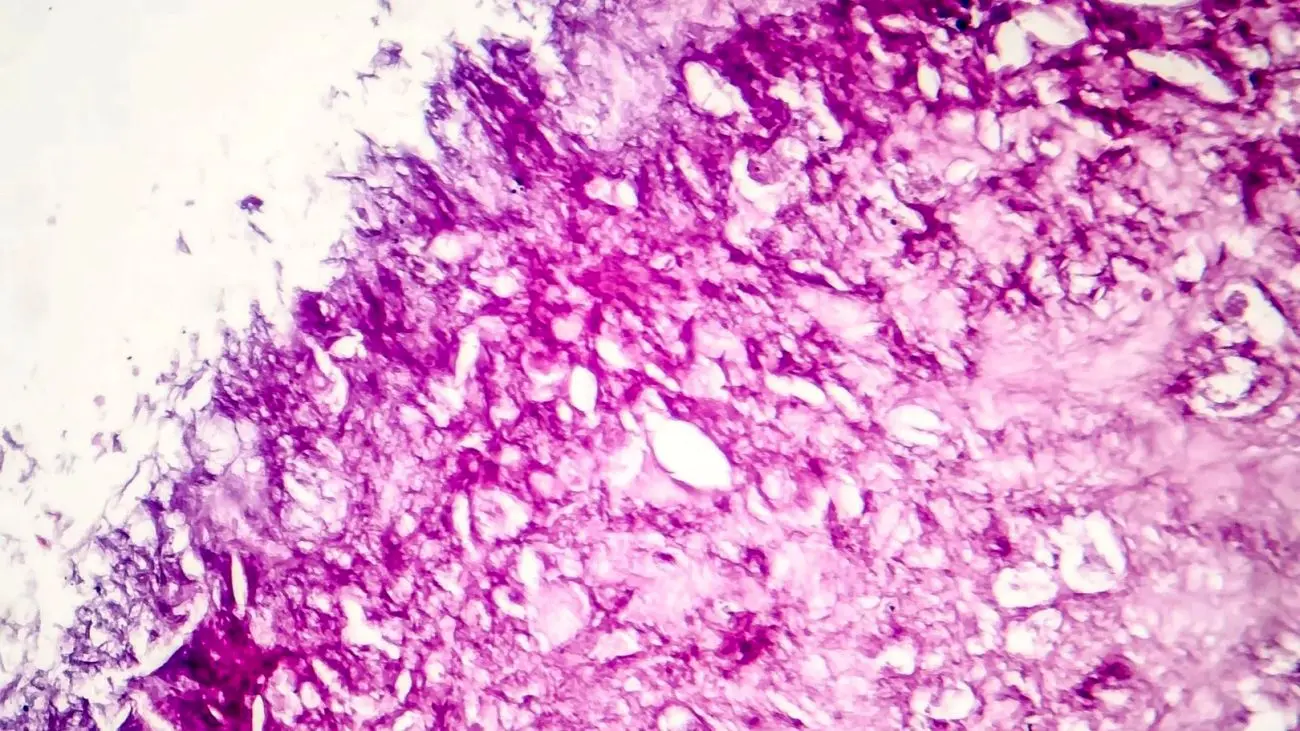

به گزارش اکوایران، دانشمندان آمریکایی اعلام کردند تحقیقات آن‌ها درباره روشی به نام «مولکول‌های ارتعاشی» باعث شده که آن‌ها بتوانند 99 درصد از سلول‌های مِلانوما‌ - نوعی سرطان پوست - را از بین ببرند.

به نوشته یورونیوز، محققان با ایجاد ارتعاش در مولکول‌ها با استفاده از نور مادون قرمز دریافتند که این روش برای از بین بردن سلول‌های ملانوما و از بین رفتن غشای سلول‌های سرطانی، موثر است.